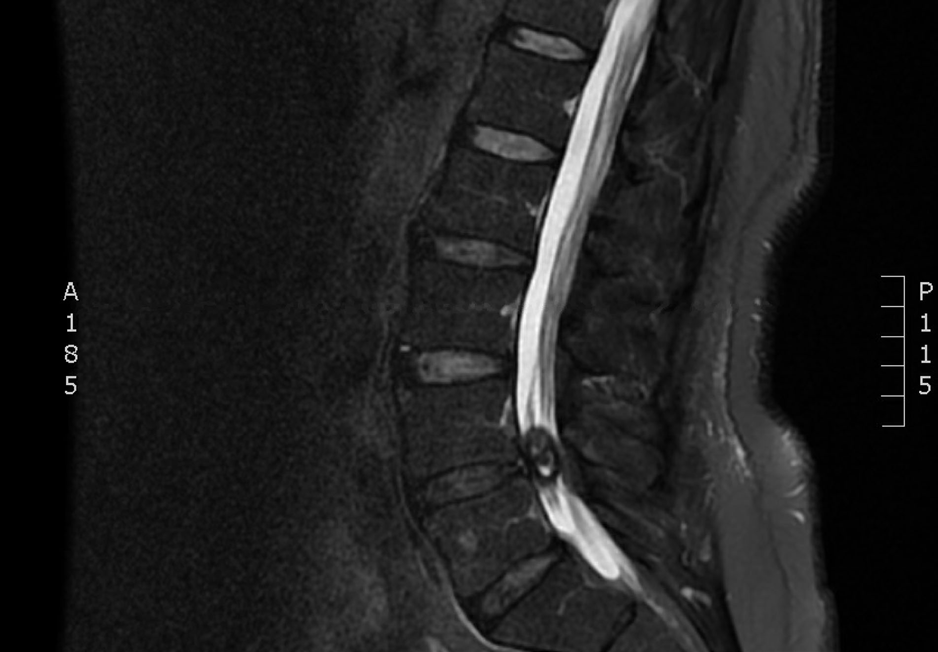

- RM lumbar inicial: condrosis degenerativa L2-S1, con abombamiento discal leve L4-L5 y quiste sinovial en la faceta articular derecha L4-L5, provocando estenosis severa del canal raquídeo.

- RM de control: resolución casi completa del quiste sinovial en L4-L5, con cambios degenerativos persistentes en articulaciones interfacetarias y discos desde L2 a S1.

Quiste sinovial facetario derecho en L4-L5 asociado a estenosis severa del canal raquídeo con resolución espontánea.

El dolor mejoró en un 90% en las semanas posteriores, logrando casi completa resolución sintomática. Al compararse estudios de RM, se evidencia la desaparición significativa del quiste sinovial. Paciente asintomático y en seguimiento por Atención Primaria.